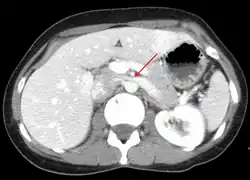

The nutcracker syndrome results from compression of the left renal vein between the aorta and the superior mesenteric artery.

Compression most commonly occurs between the abdominal aorta (AA) and superior mesenteric artery (SMA), though compression may also occur between the aorta and spine.[3][1] Risk factors include retroperitoneal cancers, abdominal aortic aneurysm, low body mass index, lordosis, and enlarged lymph nodes around the aorta.[1] Diagnostic may be suspected based on symptoms and confirmed by medical imaging after ruling out other possible causes.[1] Superior mesenteric artery syndrome is a different condition in which the duodenum is compressed between the the SMA and AA.[4]

Nutcracker syndrome is diagnosed through imaging such as doppler ultrasound (DUS), computed tomography (CT), magnetic resonance imaging (MRI), and venography.[15] The selection of the imaging modality is a step-wise process. DUS is the initial choice after clinical suspicion based on symptoms. CT and MRI are used to follow up afterwards, and if further conrfirmation is necessary, venography is used to confirm.[15]

CT and MRI

CT and MRI can be used afterward to confirm compression by the AA and SMA with comprehensive measurements of the abdominal vasculature. A "beak sign" can often be seen in CT scans due to the LRV compression. However, CT and MRI cannot demonstrate the flow within the compressed vein. These two modalities can be used to confirm other evidence for NCS such as back-up of blood flow into the ovarian veins.[14][9]